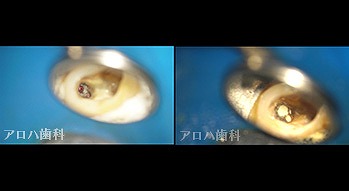

破折器具除去症例

case6

破折器具の除去 麻痺の恐れ

case7

MB根 湾曲の先に破折器具

器具の除去